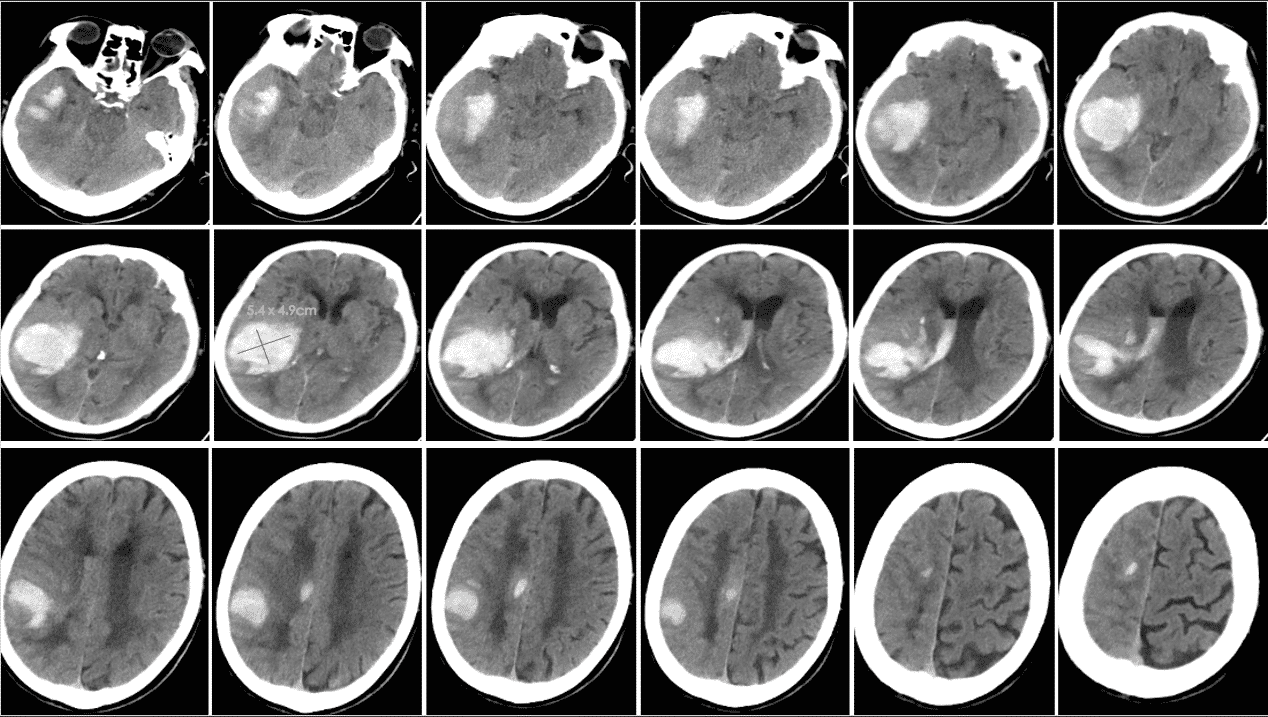

头CT(2025-7-9 13:40 本院)提示右侧颞叶、基底节区、顶叶及额叶高密度影,且破入侧脑室,考虑静脉溶栓后出血转化P2型。

⏰ 基于多田公式,粗测出血量>75ml,联系神经外科,建议手术,鉴于颅内存在动脉瘤,风险极高,家属拒绝手术方案。内科启动甘露醇联合利尿剂脱水、氨甲磺酸止血治疗,积极预防及治疗并发症。

动态观测CT变化,颅内出血及水肿情况经历 起病⇢进展⇢高峰⇢消退 动态变化,患者意识由昏迷逐渐转为嗜睡状态。三、临床诊断